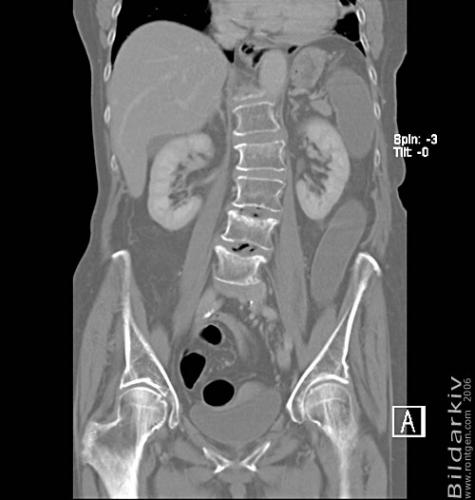

CT colon 30

Datortomografi av tjocktarmen (colon) med infunderad luft i tarmen samt med kontrast i blodbanan. Koronar bildserie.

CT multislice 16